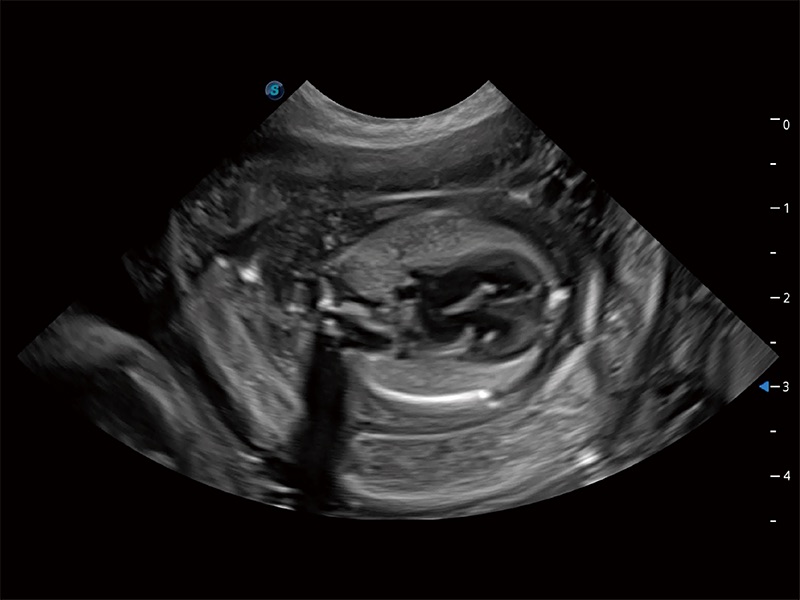

ProPet 80 配备了丰富的心脏探头群、先进的成像技术和专业的心脏测量工具,可帮助动物医生为不同体型和生理结构的动物提供心脏和心肌功能的全面评估。

实时用颜色表示心肌组织运动,观察和定量组织的运动情況,对快速检测与评估心肌的灌注和活性、电传导及心肌收缩和舒张功能等均能提供重要的诊断信息。

通过心肌识别技术与二维斑点追踪技术相结合,对心脏的超声图像进行量化分析。计算心肌17个节段的应变、应变率、速度、位移等,并通过牛眼图的形式进行呈现。

通过360度任意调节3条M型取样线,在同一心动周期上观察心脏不同位置的运动曲线,得到准确的心功能测量数据,有效评估心肌运动及左心室功能。